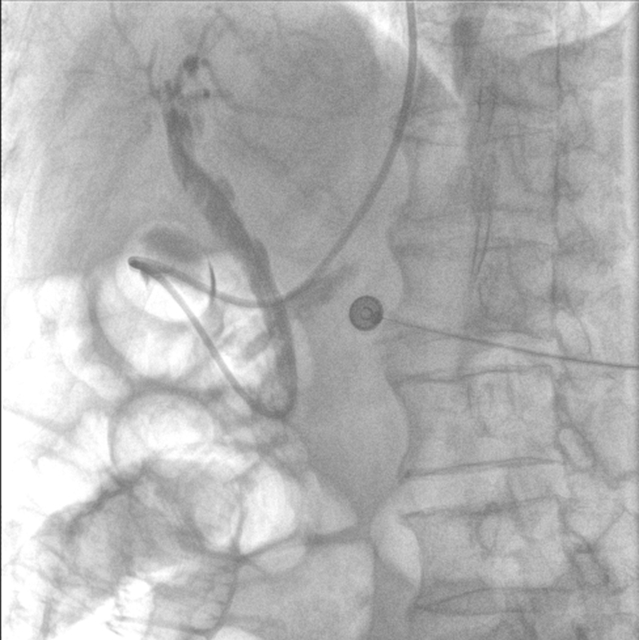

完善相关检查后,肝胆胰外科医生团队立即为张大爷实施了急诊内镜逆行胰胆管造影(ERCP)。

内镜到达十二指肠乳头时,切开乳头的瞬间,大量白色脓液喷涌而出(证实胆道高压、感染极重);随后用球囊扩张乳头(扩大开口),顺利取出嵌顿的结石。

3.精准:“可视化”操作降低风险

内镜逆行胰胆管造影全程在X光和内镜直视下完成,医生能清晰看到结石位置、乳头形态,避免盲目操作。即使结石嵌顿严重(像"卡在墙缝里的石块"),也能通过球囊扩张或机械碎石取出,成功率高达90%以上。